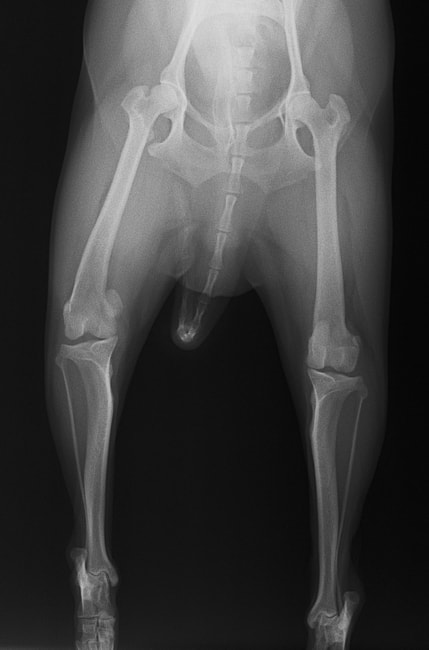

■ 症例24 キャバリア 7か月

左右膝蓋骨内方脱臼(左:グレードⅣ 右:グレードⅢ)

以前から左右後肢の跛行が認められ、整形外科学的検査・レントゲン検査により左右の膝蓋骨脱臼が認められた。症状が重度である左膝の膝蓋骨脱臼整復術を行った。外科手技は縫工筋及び内側広筋の解放、脛骨粗面の外側転位、滑車ブロック形造溝術、内外側関節方の縫縮を実施した。術後一か月時点で、左の膝蓋骨は安定しており経過は良好である。

本症例は成長期における重度の膝蓋骨脱臼であり、術後の再発の可能性もあるため、経過をしっかりと観察していく必要がある。また、今回手術を実施していない右膝に関しても経過を観察し、手術を検討していくこととする。